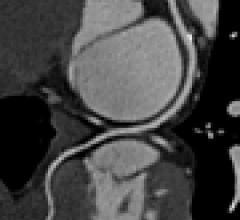

August 07, 2019This is a quick walk around of the new Siemens Somatom Go.top cardiovascular edition compact computed tomography (CT) scanner on display at the Society Of Cardiovascular Computed Tomography (SCCT) 2019 meeting in July. It is aimed at cardiology office based imaging and was released this past spring at the American College of Cardiology (ACC) meeting.

The system has removable tablets on each side of the scanner where the tech can adjust the machine, review scout scans and trigger the scanner. The idea is to improve workflow and allow the tech to remain at the bedside longer to be with the patient, rather tucked away in a remote control room using an intercom.

The entire system is built into the gantry seen here, so there is no need for extra equipment in a closet, cabinet or server tower.

It comes in a 128 slice configuration with 4 cm of anatomical coverage per rotation.

It uses the Stellar detector and tin filtration to eliminate low energy photons and help lower dose. It can be programmed to aid workflow by automatically removing bone, create cured planar reconstructions, lung CAD and other post-processing features so more time can be spent on reading scans. The scanner also comes with a HeartFlow FFR-CT starter pack.